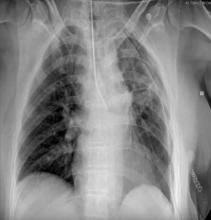

A female patient was referred to the authors’ institution for ground glass lesions in the left upper lobe and superior segment of the lower lobe. The lesions were not responsive to antibiotic therapy and exhibited interval growth. Positron emission tomography showed an FDG uptake of 2.3 in the left upper lobe. A three-port VATS left upper trisegmentectomy and superior lower lobe segmentectomy were performed. Two branches of the PA were closed and divided with a harmonic scalpel. Histological analysis showed a 0.8 cm mixed adenocarcinoma, with lepidic (70%) and acinar (30%) patterns in the upper lobe. There was no evidence of neoplasia in the lower lobe.